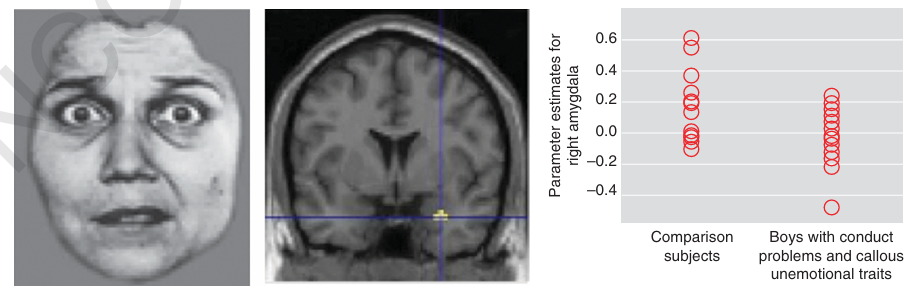

뇌과학적으로 보면, 이 아이들은 두려운 표정을 볼 때 편도체(Amygdala)의 반응이 현저히 낮게 나타납니다(Jones et al., 2009; Marsh et al., 2008). 더 흥미로운 점은 이들이 상대방의 눈을 바라보는 데 어려움을 겪는다는 것입니다(Dadds et al., 2008). 눈은 감정의 창입니다. 타인의 눈을 보지 않으니 감정을 읽지 못하고, 공감 능력이 발달하지 못하는 것이죠. 이 시기 아이들에게 필요한 것은 단순한 훈육이 아니라, 감정을 처리하는 뇌의 회로를 이해하고 그에 맞는 섬세한 중재입니다.

▲ 두려운 표정을 보았을 때 편도체 반응이 낮게 나타나는 CU 특성의 아이들(표에서 좌측). 즉, 이들은 '두려움'이라는 감정을 쉽게 이해하지 못합니다.